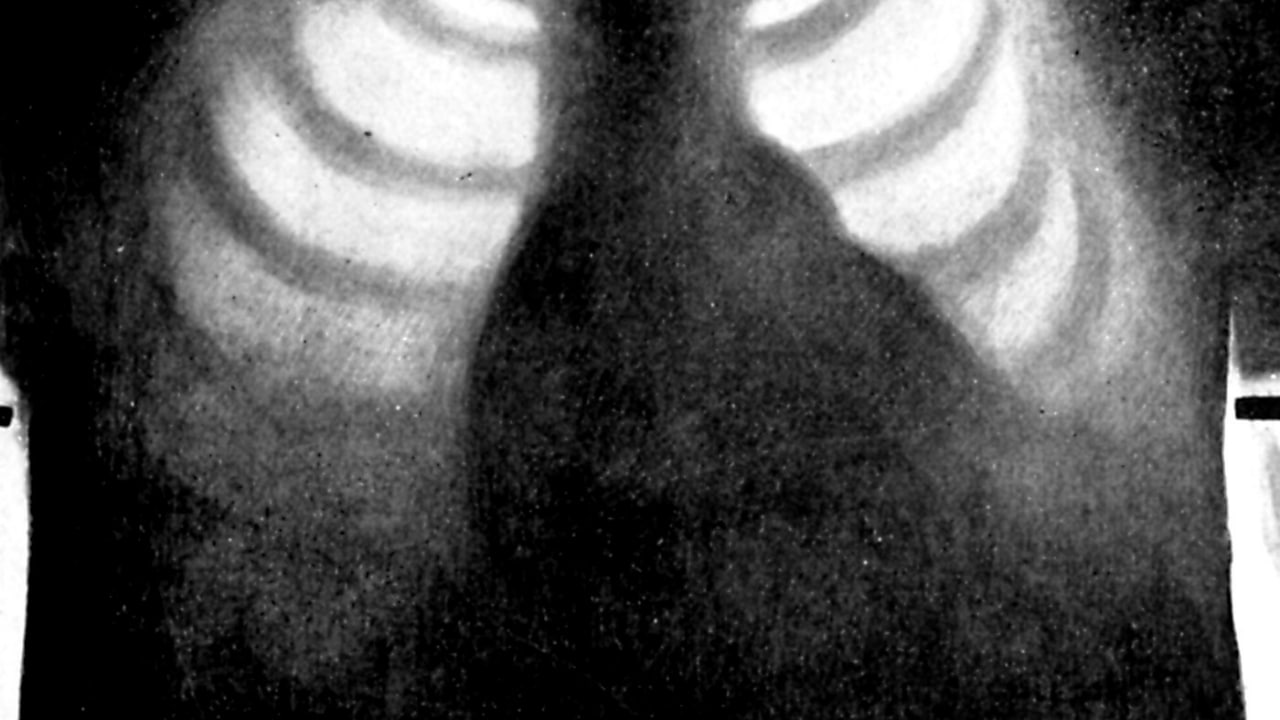

شرکت Oxipit با انتشار بیانیهای اعلام کرد ابزار هوش مصنوعی آنها که بدون کمک رادیولوژیست میتواند عکسهای اشعه ایکس قفسه سینه را بررسی اولیه کند، مجوز قانونی اتحادیه اروپا را دریافت کرده است.

با توجه به اینکه رادیولوژیستها در چند سال گذشته برای خودکارسازی کامل بخشهایی از کار خود تلاش داشتهاند و این ابزار که ChestLink نام دارد اولین هوش مصنوعی کاملا مستقل حوزه تصویربرداری پزشکی محسوب میشود، میتوان از آن به عنوان یک فناوری بسیار مهم و البته چالش برانگیز یاد کرد.

نحوه کار این ابزار نیز بسیار جالب است و پس از اسکن عکسهای اشعه ایکس قفسه سینه، گزارش بیماران سالم را به خود آنها و گزارش مواردی با یک مشکل احتمالی را برای رادیولوژیستها ارسال میکند تا توسط آنها نیز بررسی شوند.